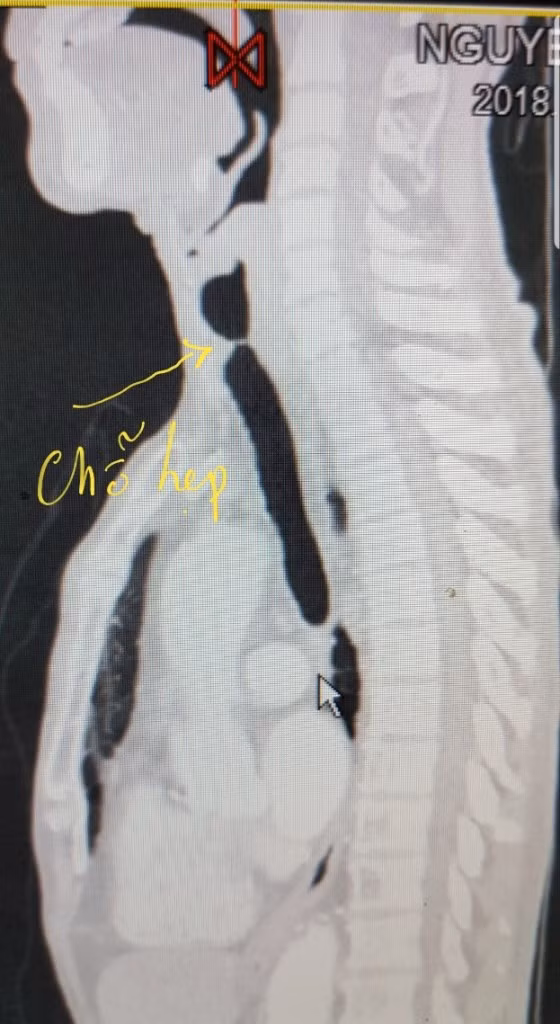

| Kết quả chẩn đoán hình ảnh cho thấy bệnh nhân bị tắc đường thở do chèn ép khí quản. |

Tại bệnh viện đa khoa TP Cần Thơ bệnh nhân được thăm khám và chẩn đoán hẹp khí quản đoạn cổ, do di chứng đặt nội khí quản lâu ngày.